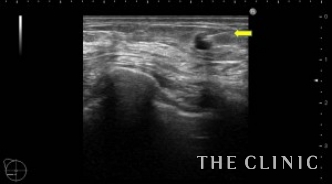

No.23でご紹介した方のオイルシストです。

エコー下にて穿刺吸引を行いました。

吸引後です。